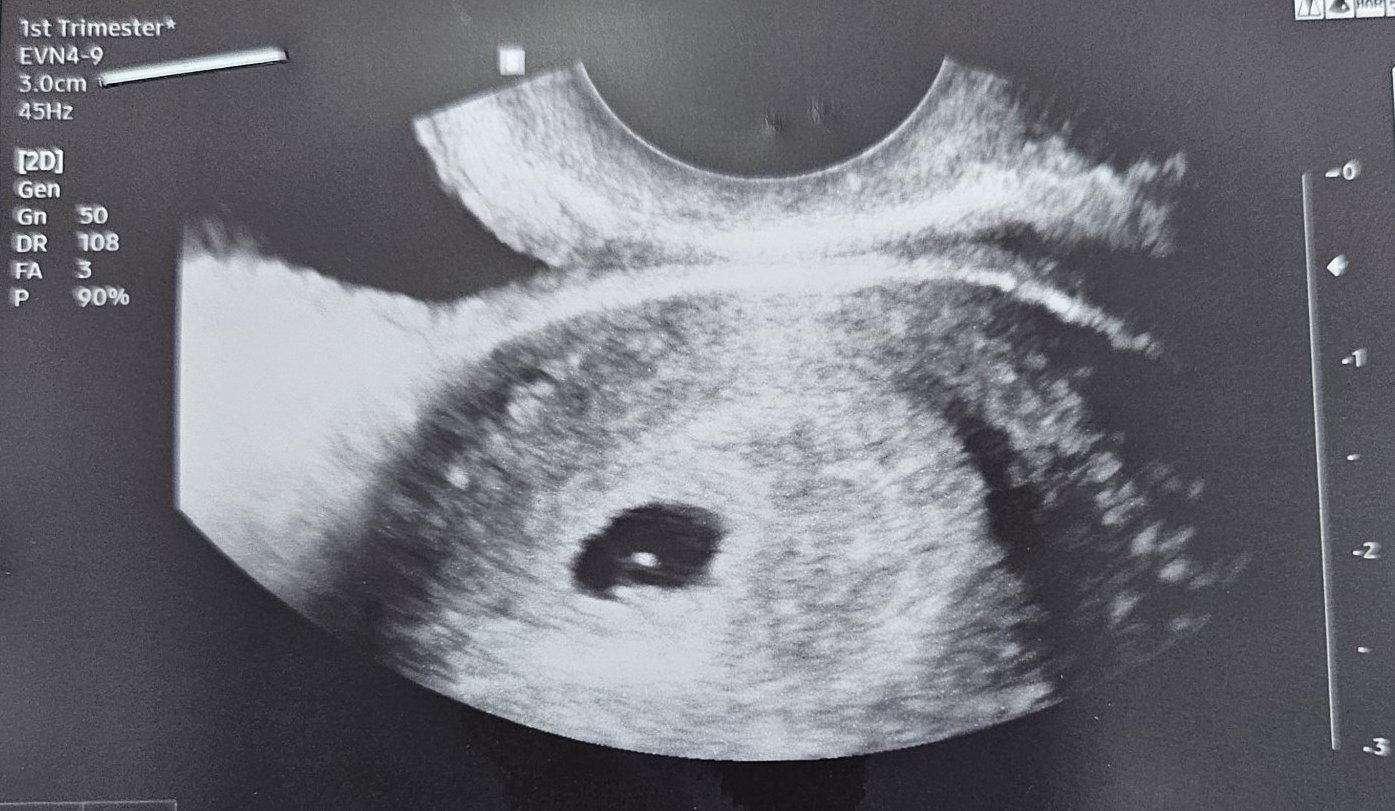

На 10.03 (понеделник) сутринта имах много оскъдно кафяво зацапване - много се изплаших и отидох на преглед. Имах еднократна болка през нощта, но не беше силна.(прилагам снимка от ехограф 1.). Гърдите ми бяха поомекнали и още тогава ми подсказа, че нещо не е наред, но според доктора това с гърдите не е фактор. И след 2 дни гърдите отново ме боляха. Назначиха ми инжекции и дуфастон вече 4×1. Зацапването спря. Днес 13.03 ме погледна отново и се видя празен плоден сак (прилагам снимка 2) Доктора каза, че това нищо не значи и е хубаво да изчакаме 2 седмици и тогава да ме прегледа отново.

По мои изчисления съм в 5г.с.+1 ден.

Кажете ми, според вас има ли шанс днес просто ъгъла да не е бил подходящ или да се е скрило някъде или е по-добре да нямам напразни надежди?